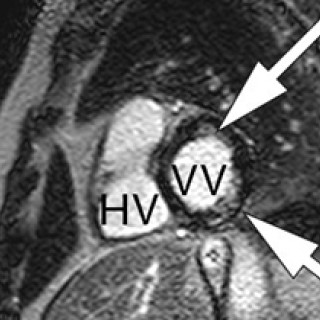

Anne Voss, Claus Manniche, Dženan Mašić et al. Reumatologi 4. utg. 543 s, tab, ill. København: FADL's Forlag, 2018. Pris DKK 800 ISBN 978-87-7749-969-2 Denne danske læreboken i revmatologi består av 27 kapitler om revmatologiske sykdommer. Rundt 50 forfattere bidrar og kommer utelukkende fra det danske revmatologiske miljøet. Målgruppen er angitt til å være leger, men også kiropraktorer, fysioterapeuter og andre med interesse for revmatologi. Boken brukes i spesialistutdannelsen for faget revmatologi i Danmark, og som oppslagsverk for ortopeder og allmennleger. Den virker også adekvat for...